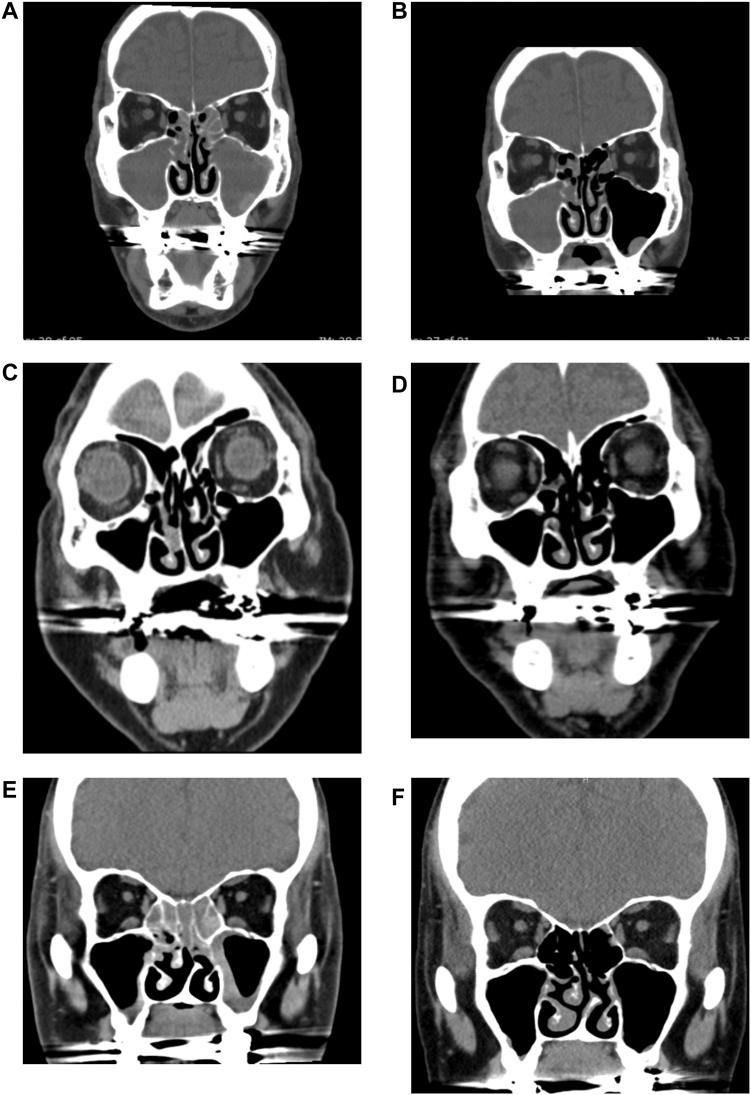

tezepelumab是一种靶向胸腺基质淋巴细胞生成素(TSLP)的单克隆抗体,可减少重度哮喘的发作。本文介绍了4例重度哮喘合并慢性鼻-鼻窦炎伴鼻息肉患者在接受tezepelumab治疗后,两种疾病均得到改善的病例。